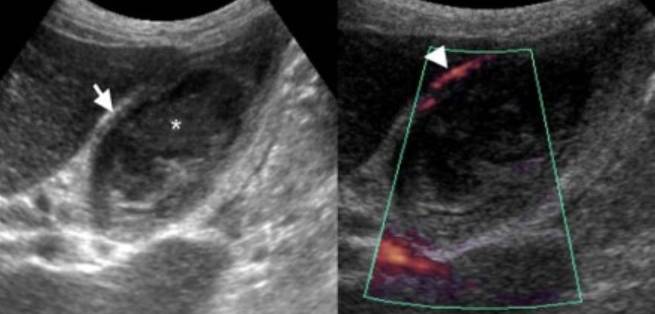

Главным способом постановки такого диагноза является ультразвуковое исследование брюшной полости (УЗИ).

Результаты этого инструментального обследования дают возможность специалисту-гастроэнтерологу поставить точный диагноз, определить форму и степень развития болезни.

Если возникнет такая необходимость, врач может назначить УЗИ в комплексе с желчегонным завтраком или прибегнуть к методу рентгенографии. Для уточнения диагноза назначаются анализы для лабораторных исследований (кровь, моча и кал).